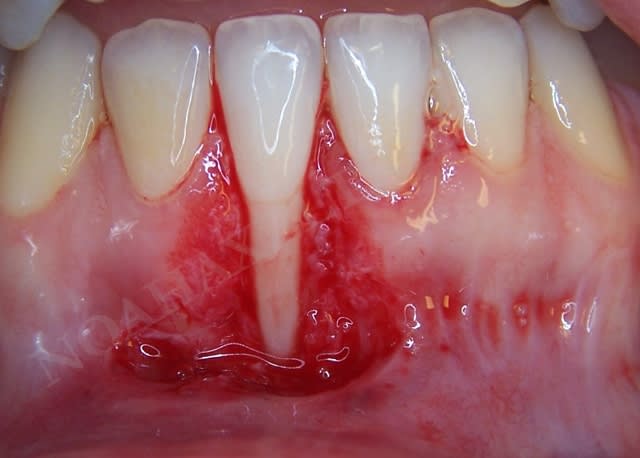

Dans le cas suivant, l'atteinte interproximale 31-41 n'autorise malheureusement aucune solution de recouvrement radiculaire :

Img 8511 llqbsh - Eugenol